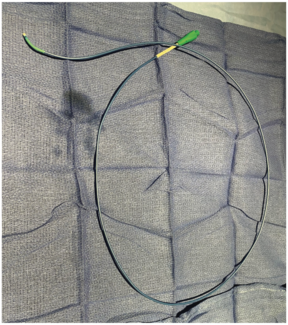

In this case, the author demonstrates the use of a low entry profile 1.5 mm PTCA balloon catheter (Takeru PTCA Balloon Dilation Catheter, Terumo Interventional Systems), used when two other low-profile microcatheters were unable to cross,...